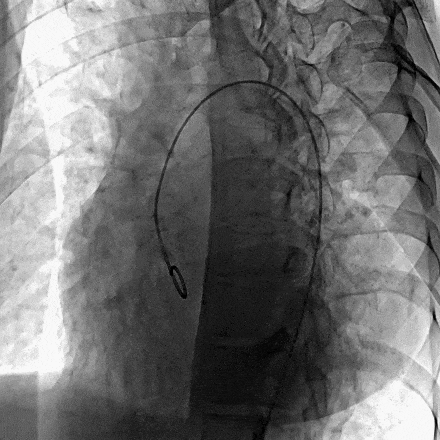

患者局麻后穿刺右股动脉及股静脉,经股动脉送入猪尾导管分别行左心室造影+主动脉根部行根部造影提示主动脉窦瘤破裂(无冠窦-右心房),持续大量左向右分流。明确病变位置后建立股动静脉轨道,经右侧股静脉送入输送鞘并送入先健12/14mm PDA封堵器。再次造影无分流,超声提示窦瘤破裂封堵完好,基本无残余分流,主动脉瓣未受影响。

术前主动脉根部造影示:主动脉窦瘤破裂(无窦-右心房),大量左向右分流